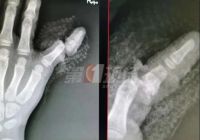

[家具相关资讯] 防不胜防,别让你家的柜门再吃人了!

#宝宝手指被门夹断# 家长是不是经常被这样的新闻吓懵了! 可现实生活中却常常上演 博主Oliva分享,她在关门时,没有留意女儿跑到妈妈的背后,这时孩子的手指放在门缝里,门快速关上...